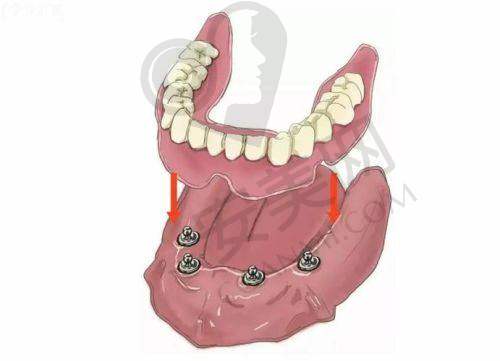

all - on - 4半口种植牙是一种精良的牙齿种植技术。它通过在牙槽骨内植入4颗种植体,然后利用这4颗种植体支撑起半口的牙桥。与传统的种植牙技术相比,all - on - 4半口种植牙具有诸多优势。首先,它大大减少了种植体的植入数量,降低了手术的创伤和风险。其次,手术时间相对较短,患者的修复时间也更快。此外,这种技术能够在当天完成种植和修复,让患者尽快修复牙齿的咀嚼功能和美观度。